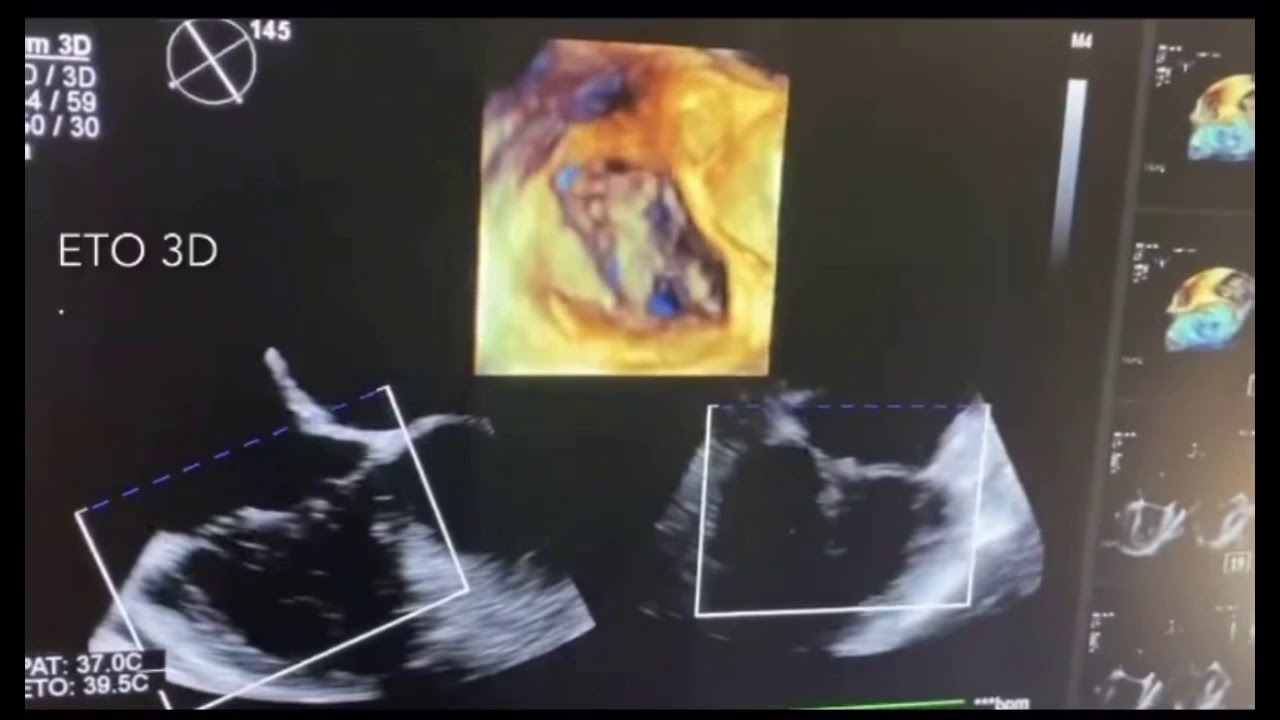

La valve tricuspide est une valve cardiaque sujette à des valvulopathies, telles que le rétrécissement et l'insuffisance tricuspide, avec des examens et traitements disponibles. Tandis que les indications pour la gestion chirurgicale de l'insuffisance tricuspide sévère sont maintenant généralement acceptées. L'insuffisance tricuspidienne se produit habituellement sur une valve normale affectée par une dilatation du ventricule droit.

Valves aortiques Banque de photographies et d’images à haute résolution Alamy. Elle peut être liée à une dysfonction primaire de la valve, ou secondaire à l'hyper­tension pulmonaire ou à une maladie de la valve mitrale Transcatheter valve interventions on the mitral and tricuspid valves entail increasing complexity